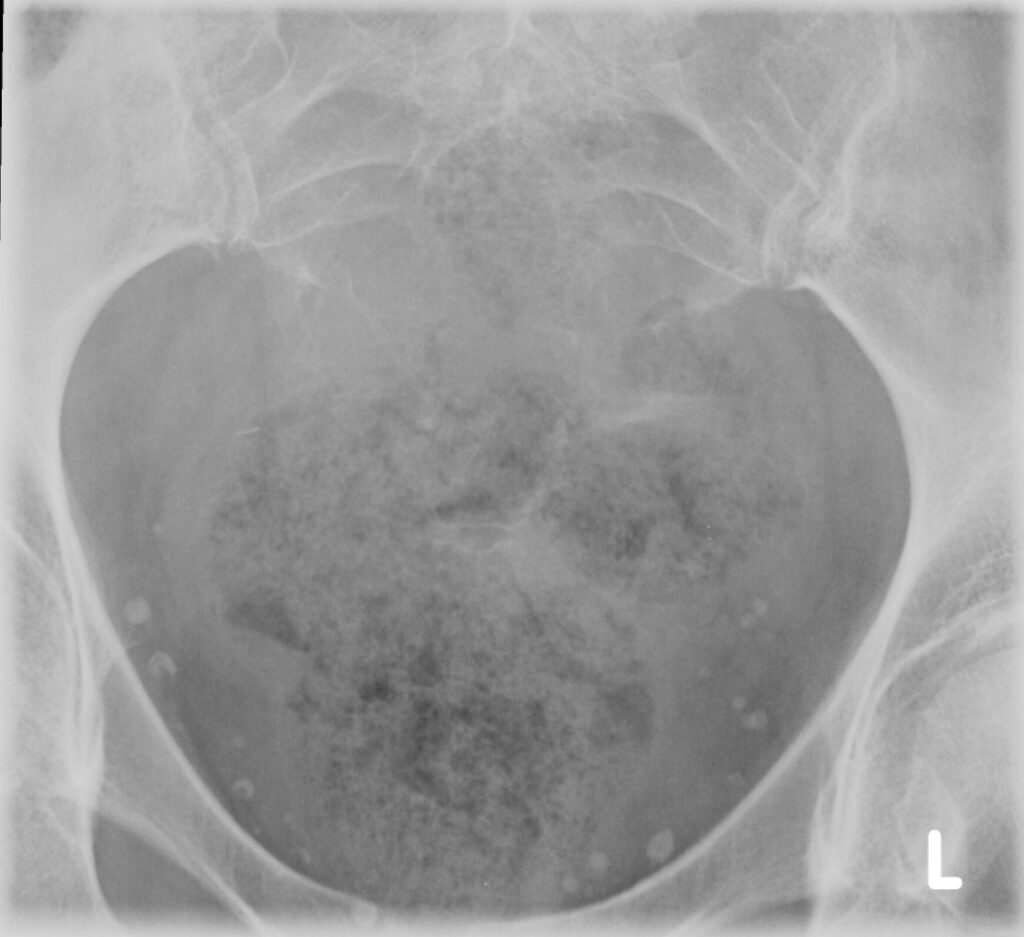

Plain x-ray (Fig. 1-3)

• Midline bone lytic lesion with focus in the vertebral body

• Surrounding soft tissue mass

• Invade intervertebral discs and contiguous vertebras.

Fig. 1-3: Plain X-ray of the sacrum demonstrates a chordoma. There is a lytic lesion of the sacrum with total destruction of the sacrum.